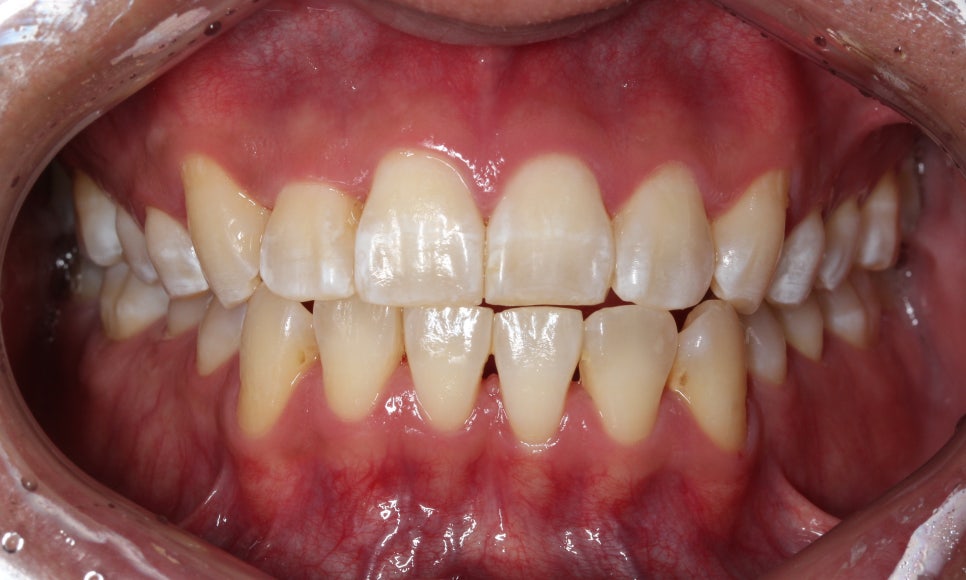

이번에는 덧니 고민으로 오신 환자분인데요.

윗니 오른쪽 두 번째 앞니가 들어가 있고,

다른 앞니끼리도 너무

세게 닿아서 고민이라고 오셨어요.

사진을 보실 땐

눈에 보이는 방향의 왼쪽이

환자에게는 오른쪽입니다.

첫 방문 때 이렇게 아래 앞니도 깨져있고,

#12 치아는 안으로 들어가 있었습니다.

환자분은 #13 이 튀어나왔다고 생각하시던데,

이렇게 씹는 면 사진으로 보면

#13이 튀어나왔다라기보단

#12가 상대적으로 들어가 있는 게 맞죠.

치주치료도 필요하신 분이고,

충치치료도 필요한 부분들이 보였습니다.